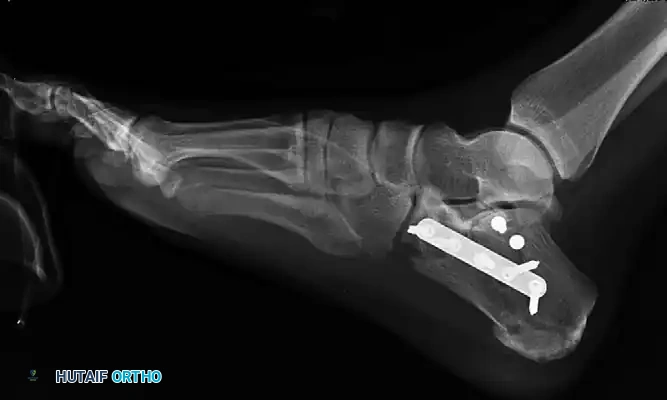

Figure 88-12: Radiographic demonstration of definitive fixation utilizing both medial and lateral plates to buttress the reconstructed calcaneus.

Lateral Fixation

- Posterior Facet: Return to the lateral incision. Replace the provisional K-wires across the posterior facet with definitive lag screws, securing the facet to the sustentacular fragment.

- Lateral Wall: The lateral wall is often too thin and comminuted for lag screw fixation. Apply a small 1/3 tubular plate or a low-profile Wave plate (Tornier, Inc., Edina, MN) to buttress the lateral wall. Screws can be inserted subcutaneously to minimize hardware prominence.